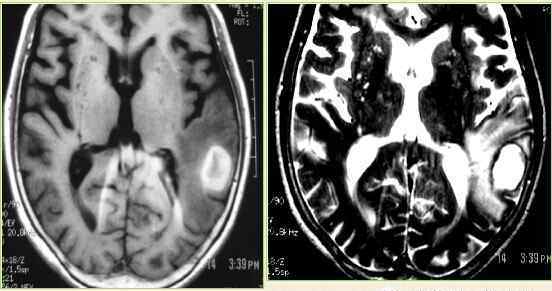

急性脑出血在CT上定位准确,是高密度图像。

诊断:高血压脑出血多见于50岁以上的高血压患者。常因情绪激动、脑力过度、体力劳动或其他因素引起血压急剧升高,导致患病脑血管微动脉瘤破裂出血,患者突然出现意识障碍、头痛、偏瘫等。头部CT应及时进行,以鉴别脑出血或脑梗塞,出血可破入脑室或并发脑积水。